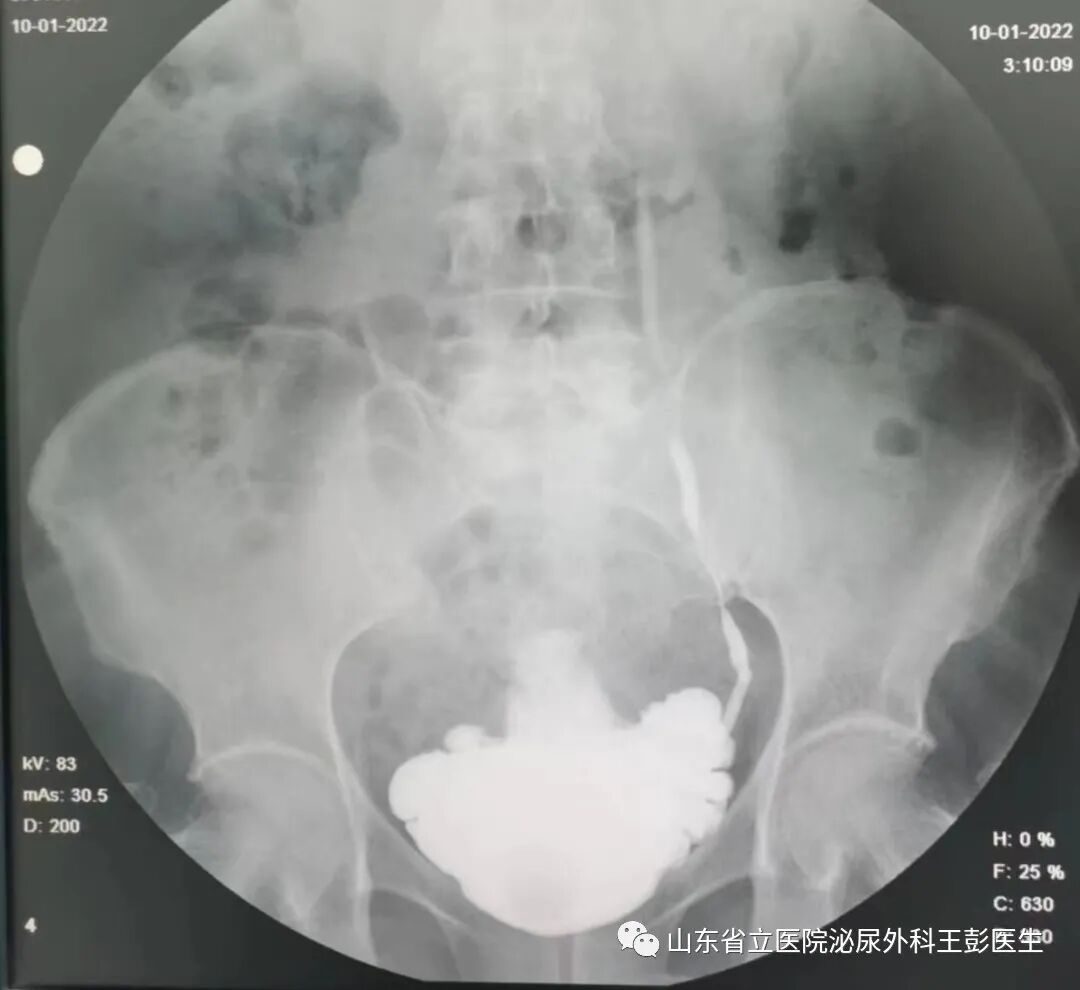

表述到这里,我们高度怀疑王女士得了排尿功能障碍所致的比较严重的并发症-肾输尿管返流。这种病直接危害到肾功能,不加干预极有可能发展成肾功能衰竭。这种病的成因非常复杂,详细询问病史后了解到,王女士两年前行妇科肿瘤手术,术后出现排尿排便困难、尿频尿不尽,夜尿达10余次并有尿失禁情况,至此我们分析患者为盆底神经损伤后导致神经源性膀胱,从而出现一系列症状。进一步完善相关辅助检查发现,患者膀胱重度脊梁化,灌注约200ml即出现左侧的输尿管返流,这便是患者出现腰痛的原因所在。

经过综合考量,我们决定为患者行双侧骶神经刺激器植入术术后患者膀胱容量恢复到约500ml,没有输尿管返流情况,同时尿频尿不尽的情况也得到极大缓解。

图片图片

术前VS术后